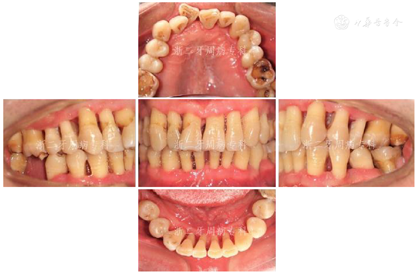

2008年9月:基础治疗完成后6个月牙周复诊,进行再评估,患者口腔卫生状况良好,牙龈炎症明显改善,PD≥7 mm的位点数从108个减少到4个,4~6 mm的位点数从61个减少到39个,平均探诊深度从7.0 mm降至3.0 mm,尤其是17远中2个位点,PD从12 mm分别降至3 mm(颊侧)与4 mm(舌侧);BOP(+)%从100%降到28.6%(图8)。各牙松动度较治疗前也明显改善,下前牙31、41仍有0.5 mm间隙。

2009年4月:牙周基础治疗后1年复诊。患者口腔卫生可,牙龈色粉质韧,仅下前牙舌侧可见少量软垢,局部龈缘充血(图9),并惊喜地发现:下前牙31、41间隙已完全关闭。牙齿松动度、PD、BOP(+)%与半年前无明显变化(图10)。全口曲面体层X片示:牙槽嵴顶硬骨板较2007年12月清晰,14、17、24、34、36局部有牙槽骨修复、36根尖周骨密度增加,其余位点牙槽骨均未见进一步吸收;46缺牙区牙槽骨密度和高度增加(图11),提示牙周基础治疗后牙周状况得到了明显改善。因37、46缺失牙未及时修复,16略伸长,38近中倾斜,再次建议患者正畸治疗,直立38、压入16,排齐整平牙列,修复缺失牙37、46。患者拒绝正畸和修复治疗。予以16调磨、牙周维护治疗、35~44超级粘结剂牙周固定。

2011年4月:牙周基础治疗后3年复诊。患者口腔卫生维护佳,牙周状况良好,牙龈色粉,无明显红肿,口内未见明显结石与软垢(图13),牙齿松动度牙周袋进一步变浅,PD≥7 mm位点消失,4~6 mm的位点数进一步减少,仅有6个位点,BOP(+)%仅为6.5%(图14)。全口曲面体层X片示:牙槽骨硬骨板较明显,牙槽骨无进一步吸收迹象;37、46缺牙区牙槽骨高度无明显降低(图15)。检查结果显示,患者牙周状况已经稳定。予以牙周维护治疗、复发危险评估,评估结果为中度(图16),嘱患者继续保持口腔卫生,随访时间可延长至9~12个月。